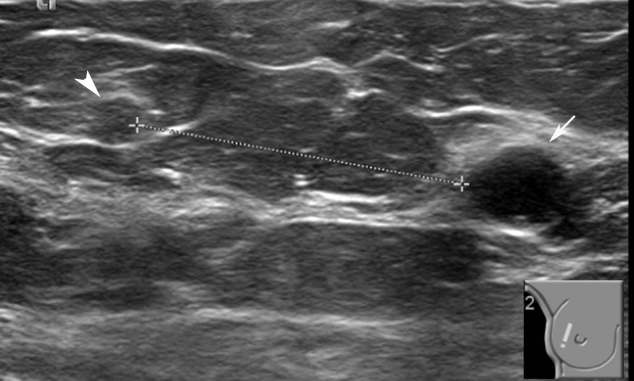

Figure 2: US imaging in 2015. At 10 o’clock, a cystic lesion seen, measuring 12x8mm (arrow). No internal vascularity identified with the use of power Doppler or wall-thickening. It was graded as U2 in the UK 5-point grading system (equivalent to BIRADS-3). The fine needle aspiration showed cystic content without evidence of malignancy (C2). 30mm apart from the cystic lesion (arrow head), a well-defined isoechoic nodule also noted, measuring 5x4mm. It did not show significant vascularity in the power Doppler. An inspissated cyst and a papillary lesion were in the differential diagnosis. It was graded as U3 in the UK 5-point grading system) (equivalent to BIRADS-4a). A 14G core biopsy performed that showed an infarcted papillary lesion, which in the immunochemistry showed no atypia (B3) and it was subsequently excised with an US guided vacuum system.

During the breast screening program in 2015, a 60-year old Bangladeshi lady was recalled for further investigation, as two relatively well-defined, isodensity opacities were identified in the mammograms of the right breast, measuring 12 mm and 5 mm (Figure 1). In the subsequent US examination (Figure 2), at 10 o’clock, a thin-walled cystic lesion noted measuring 12x8 mm. No internal vascularity was identified with the use of power Doppler. The lesion was graded as U2 in the 5-point UK classification system (equivalent to BIRADS-3) and was aspirated to dryness with the use of a 21-gauge needle [10]. Τhe content was slightly blood-stained and was sent for cytology, which was reported as C2 (normal cystic content). Additionally, 30 mm apart from the cystic lesion, a 5mm well-defined isoechoic nodule was identified, without significant vascularity in the power Doppler. An inspissated cyst and a papillary lesion were in the differential diagnosis and were graded as U3 in the 5-point UK classification system (equivalent to BIRADS-4a) [10]. A 14-gauge needle core biopsy was performed that showed an infarcted papillary lesion, without atypia. Following this, an US-guided vacuum excision with a 10-gauge needle took place and a marker clip was deployed at the side. The patient returned to routine screening.